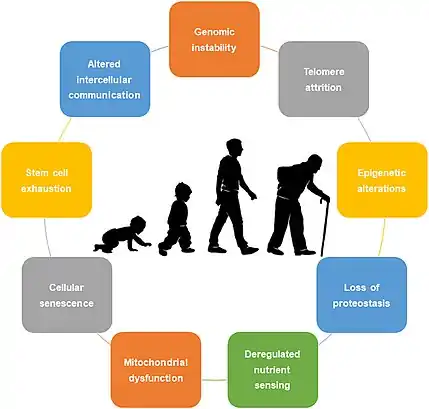

Aging is characterized by a progressive loss of physiological integrity, leading to impaired function and increased vulnerability to death. The hallmarks of aging are the types of biochemical changes that occur in all organisms that experience biological aging and lead to a progressive loss of physiological integrity, impaired function and, eventually, death. They were first listed in a landmark paper in 2013[1] to conceptualize the essence of biological aging and its underlying mechanisms.

The following three premises for the interconnected hallmarks have been proposed:[2]

Over time, almost all living organisms experience a gradual and irreversible increase in senescence and an associated loss of proper function of the bodily systems. As aging is the primary risk factor for major human diseases, including cancer, diabetes, cardiovascular disorders, and neurodegenerative diseases, it is important to describe and classify the types of changes that it entails.

After a decade, the authors of the heavily cited original paper updated the set of proposed hallmarks in January 2023.[3][2] In the new paywalled review, three new hallmarks have been added (not included or categorized below): disabled macroautophagy, chronic inflammation and dysbiosis, totaling 12 proposed hallmarks.[2]

The nine hallmarks of aging of the original paper are grouped into three categories as below:[1]

Primary hallmarks (causes of damage)

- Genome instability

- Telomere shortening (or[2] telomere attrition)

- Epigenetic alterations

- Loss of proteostasis

Antagonistic hallmarks (responses to damage)

Integrative hallmarks (culprits of the phenotype)

- Stem cell exhaustion

- Altered intercellular communication

Primary hallmarks are the primary causes of cellular damage. Antagonistic hallmarks are antagonistic or compensatory responses to the manifestation of the primary hallmarks. Integrative hallmarks are the functional result of the previous two groups of hallmarks that lead to further operational deterioration associated with aging.[1]